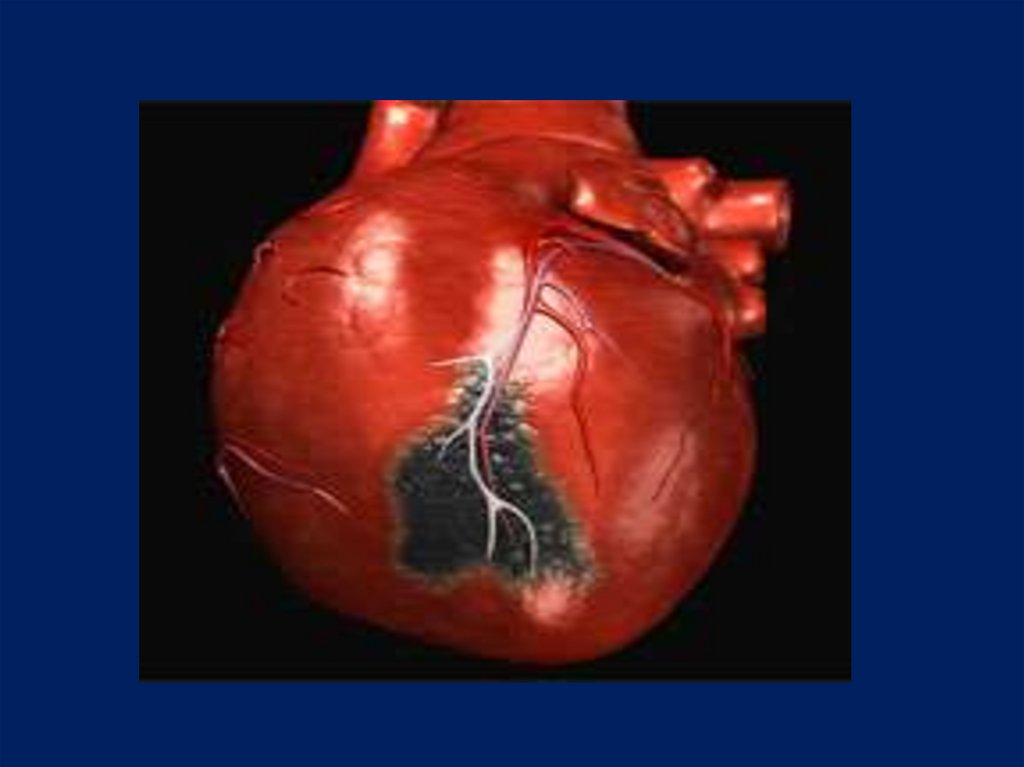

35. Значение тромбоза:

Благоприятное значение: например при

тромбозе аневризмы, когда тромб

«укрепляет» ее стенку.

Обтурирующие тромбы в артериях могут

стать причиной инфаркта или гангрены.

Пристеночные, медленно образующиеся

тромбы даже в крупных артериальных

стволах могут не вести к тяжелым

последствиям, так как в таких случаях

успевает развиться коллатеральное

кровообращение.